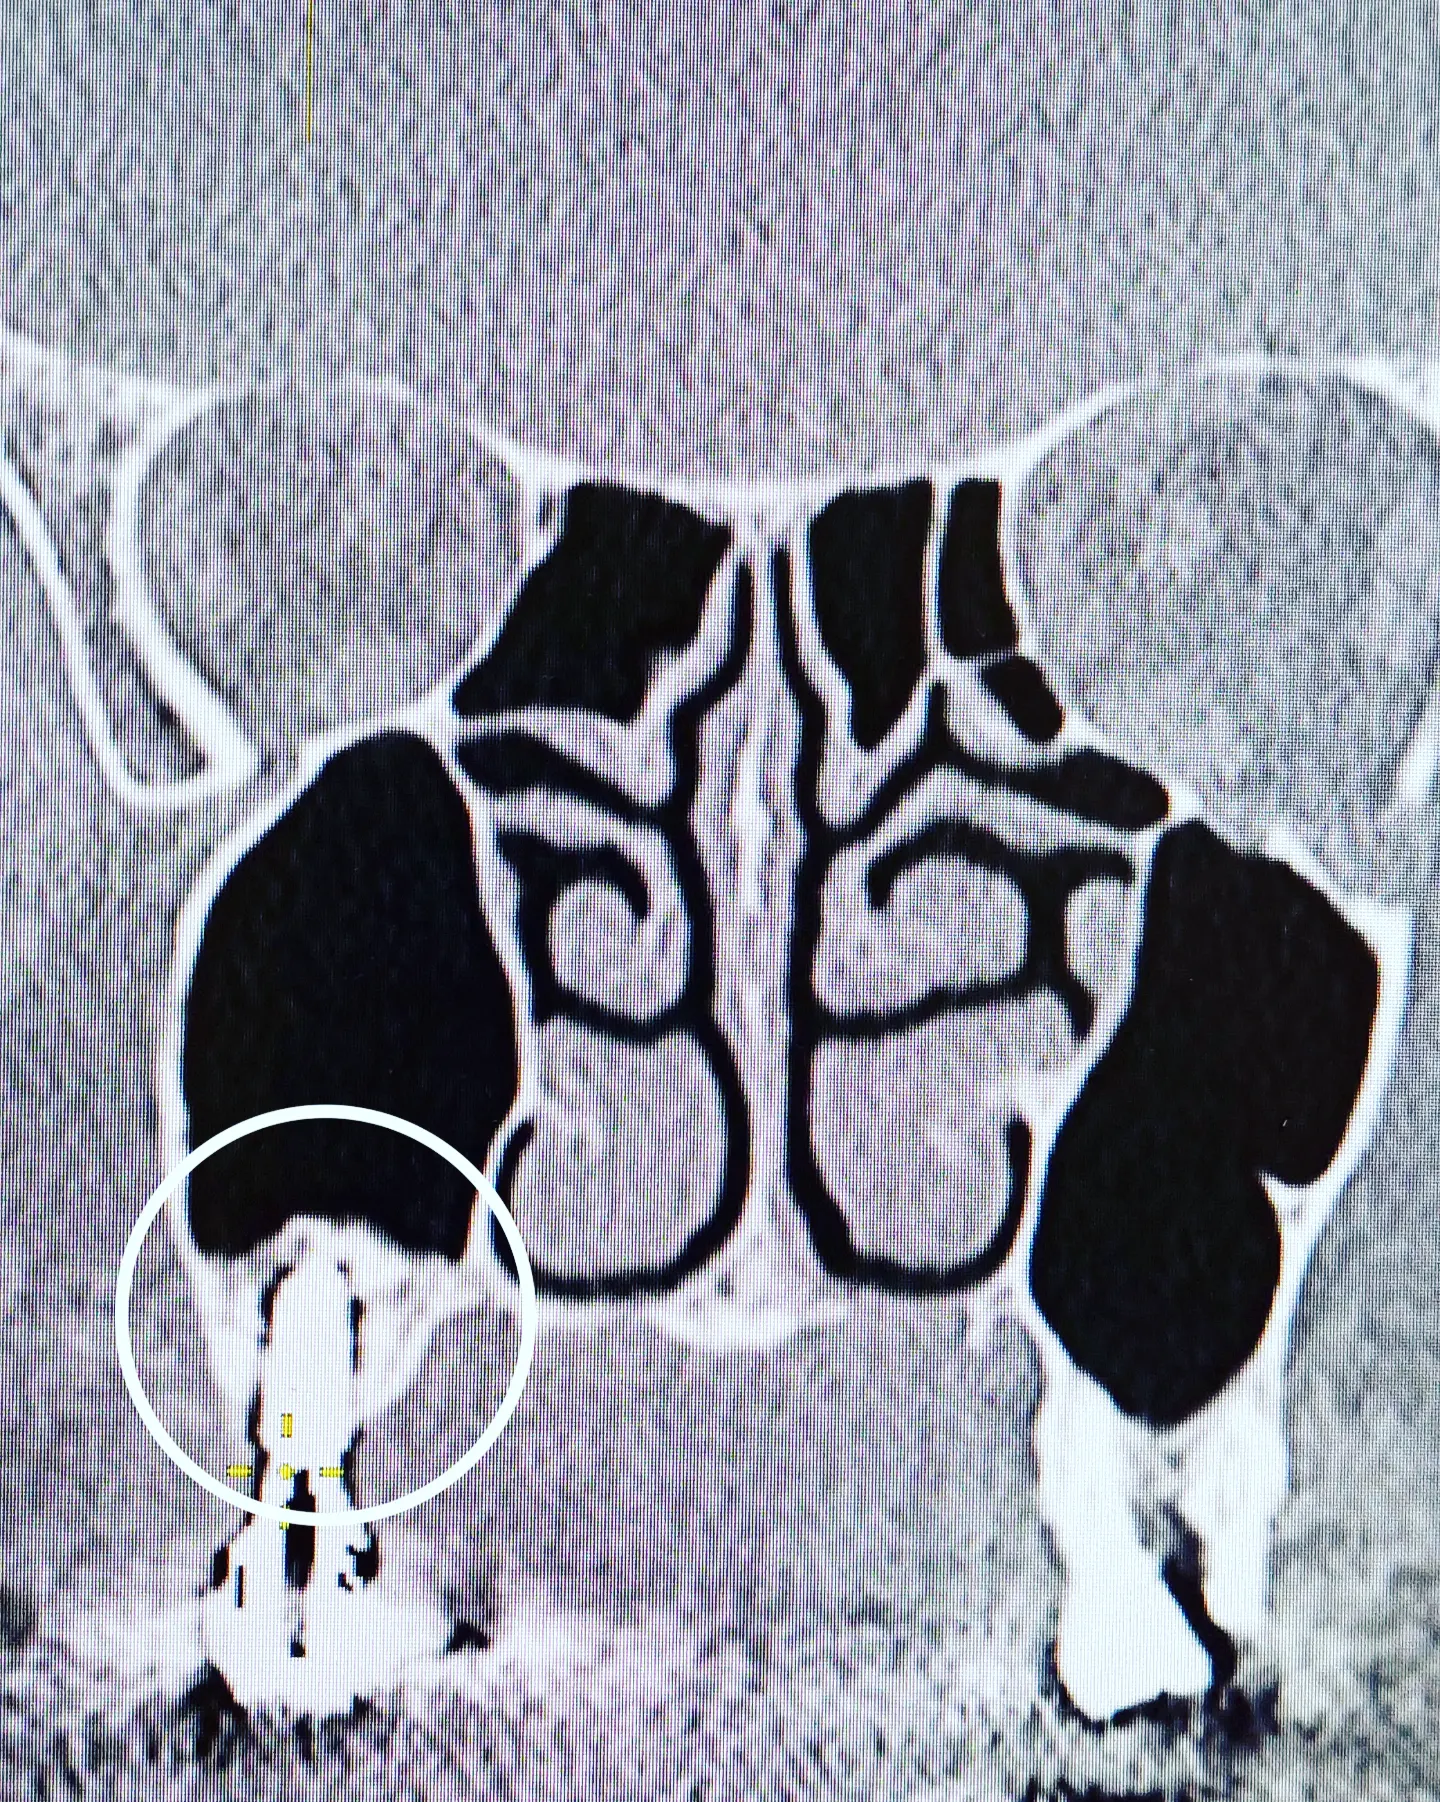

Немного занимательной стоматологии в ЛОР-практике. На приеме был пациент, которому ранее был выполнен синус-лифтинг (вдруг кому интересно как это выглядит).

Синус-лифтинг - операция по наращиванию костной ткани на верхней челюсти, когда ее не хватает для установки имплантов зубов. Почему её приходится делать? Если в челюсти отсутствует зуб, то со временем (при отсутствии нагрузки на челюсть в этом месте) атрофируется костная ткань. Для установки импланта необходимо минимум 10 мм костной ткани до гайморовой пазухи. В противном случае, показано поднятие ее дна - синус-лифтинг.